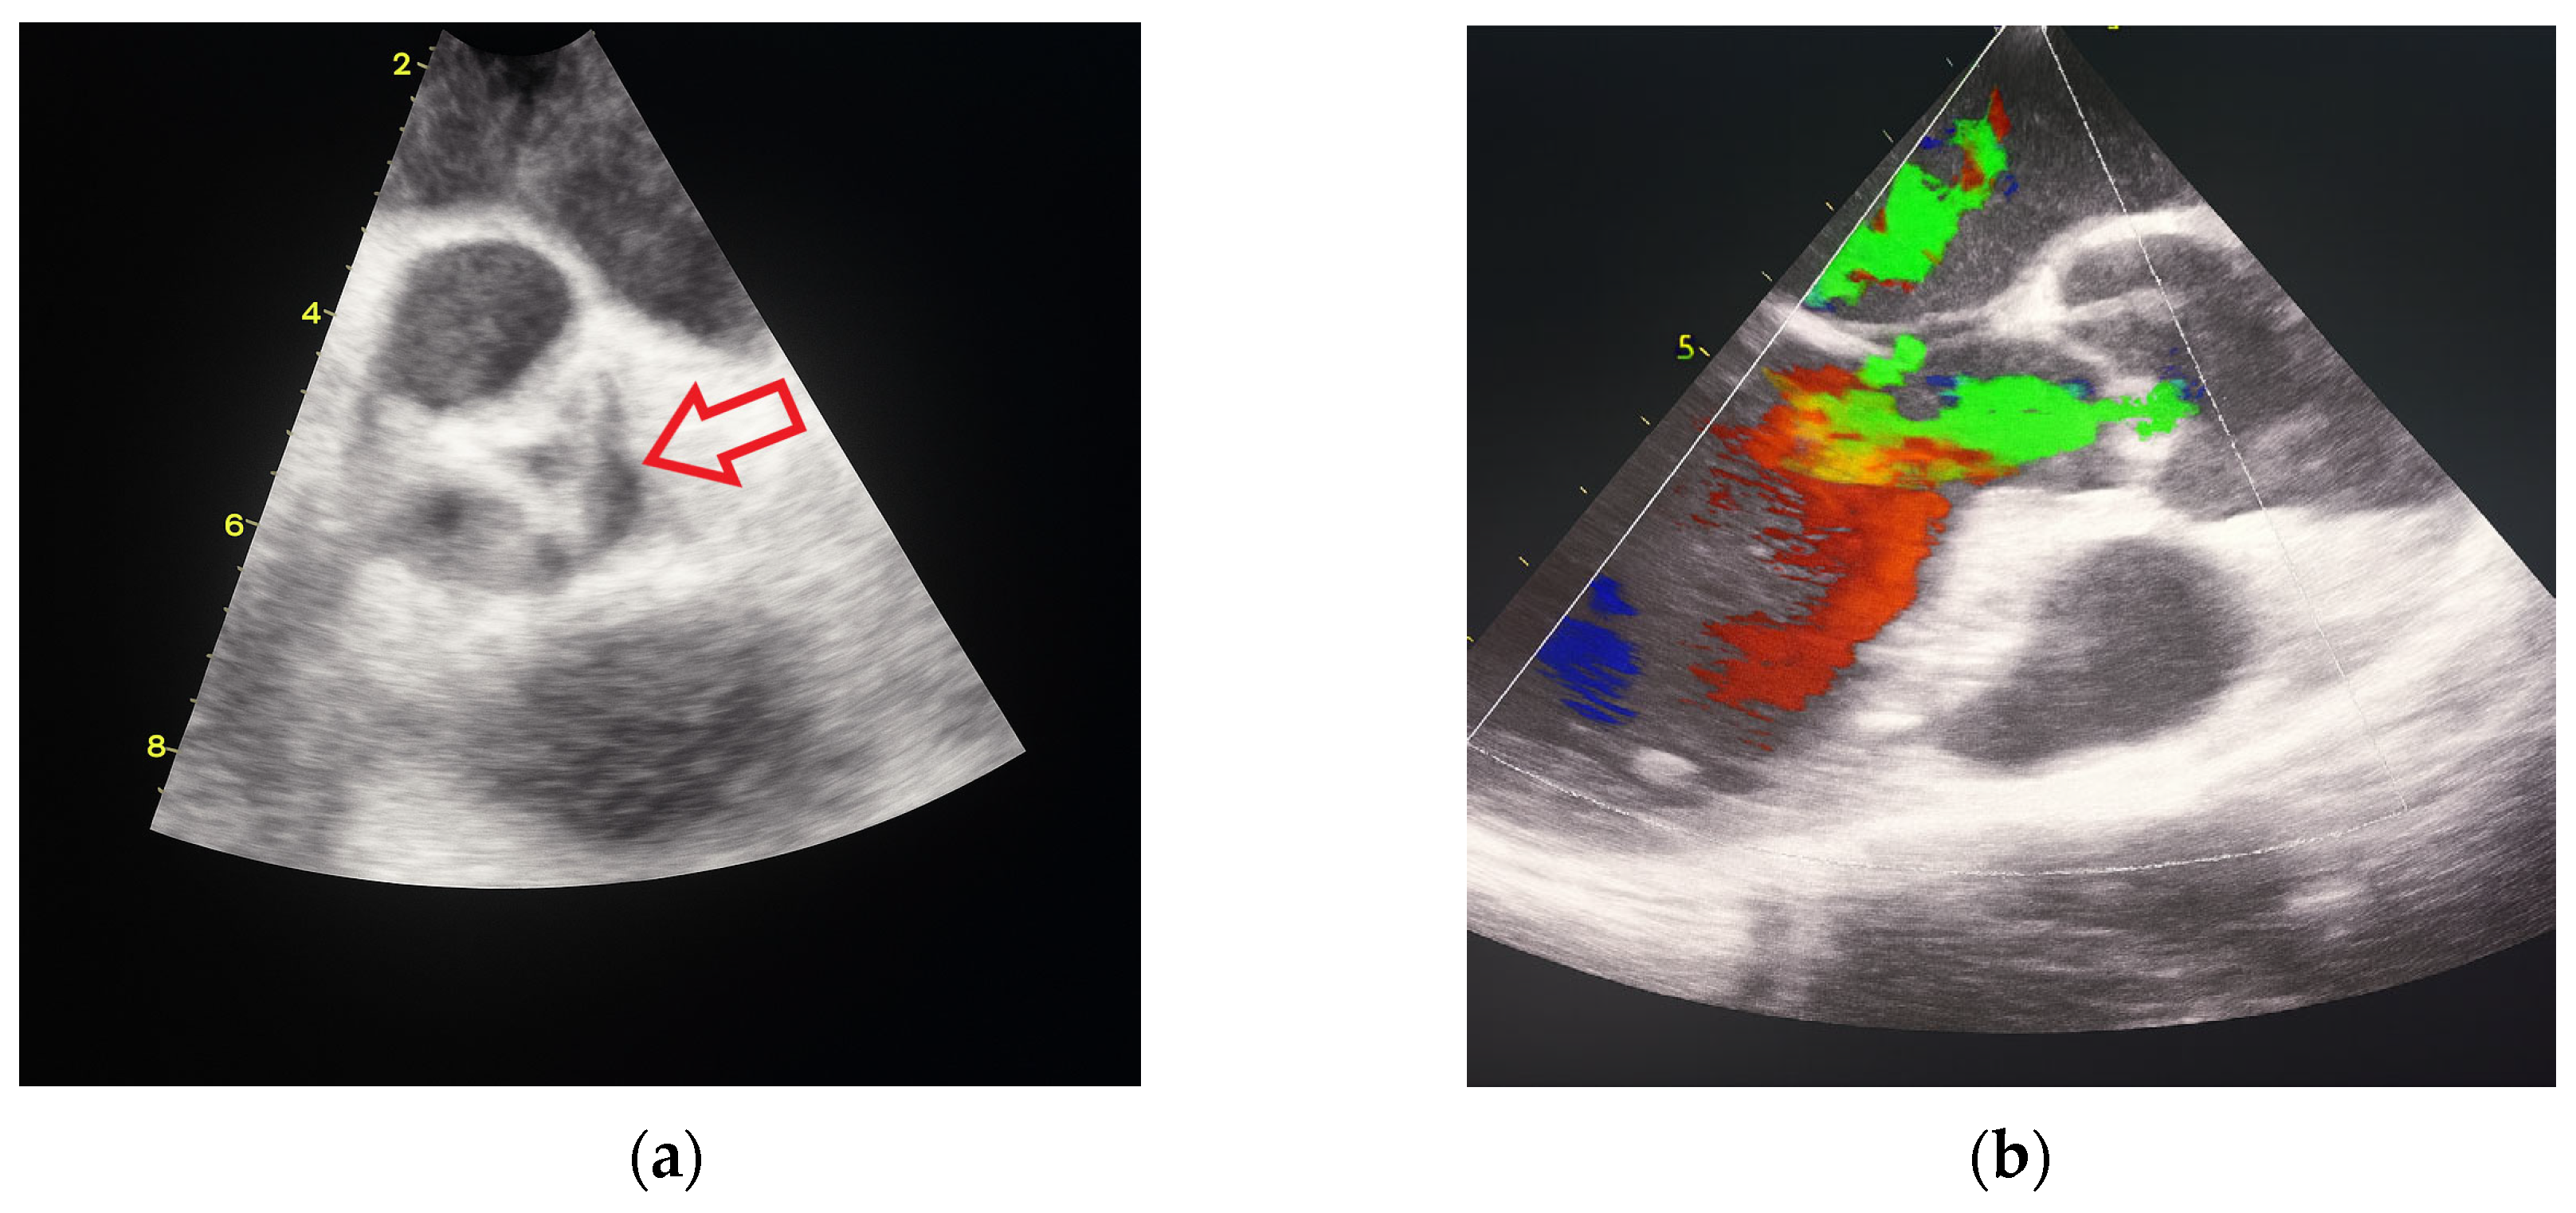

In October 2024, the patient was admitted to our Division of Rheumatology and Immunology due to exacerbation of her underlying overlap syndrome, demonstrating moderate to high disease activity: Disease Activity Score 28-ESR was 4.95 and Systemic Lupus Erythematosus Disease Activity Index was 6. Clinical symptoms included continuous moderate chest discomfort and worsening dyspnea upon exertion. She denied gastrointestinal or respiratory complaints, fever, or systemic signs of infection. Her long-term pharmacotherapy regimen included prednisone 7.5 mg/day, pantoprazole 40 mg/day, atorvastatin 20 mg/day, cholecalciferol 20,000 IU weekly, furosemide 40 mg/day, and lercanidipine 10 mg/day. Vital signs on admission were stable: blood pressure 140/90 mmHg, heart rate 76 bpm, and temperature 36.7 °C. Cardiovascular auscultation revealed a grade 2/6 systolic murmur over the precordium. Musculoskeletal examination was notable for bilateral wrist synovitis, bilateral shoulder pain with restricted range of motion, right knee arthralgia with limited mobility, and fixed flexion deformities of the right-hand fingers and left elbow. There was no clinical evidence of peripheral edema. Laboratory evaluation revealed: leukocytes 6500/µL, hemoglobin 88 g/L, platelets 188,000/µL, C-reactive protein (CRP) 11.7 mg/dL, erythrocyte sedimentation rate (ESR) 50 mm/h, hypocomplementemia (low C3 and C4), serum urea 4.9 mmol/L, and serum creatinine 144 µmol/L. Immunological testing showed negative RF and ACPA. Antinuclear antibodies (ANA) were positive at a titer of 1:160 with a homogeneous nuclear staining (AC-1 pattern). Anti-dsDNA was markedly elevated (86 IU/mL), and antiphospholipid antibodies (aPL), including lupus anticoagulant (LA), were triple positive. All other extractable nuclear antigens tested negative. High-sensitivity troponin I was elevated (84.0 ng/L), whereas N-terminal pro b-type natriuretic peptide (NT-proBNP) remained within normal limits (68.5 ng/L), and ECG findings were unremarkable. Due to persistent anemia, dyspnea, and dysphagia, repeat esophagogastroduodenoscopy was performed, confirming histologically proven erosive Helicobater pylori-negative gastritis. Repeat MSCT coronary angiography again ruled out acute coronary syndromes. Repeat TTE revealed a degenerative bicuspid aortic valve with a rudimentary left coronary cusp and moderate AR (aortic valve area: 2.4 cm2; vena contracta: 4 mm). Transesophageal echocardiography (TEE) confirmed these findings and offered a more detailed evaluation of valvular morphology and the severity of AR (Figure 2 and Figure 3).

Figure 3. Transesophageal heart ultrasound 3D imaging. (a) 3D reconstruction of the aortic root and ascending aorta. (b) 3D Color Doppler imaging of aortic regurgitation.